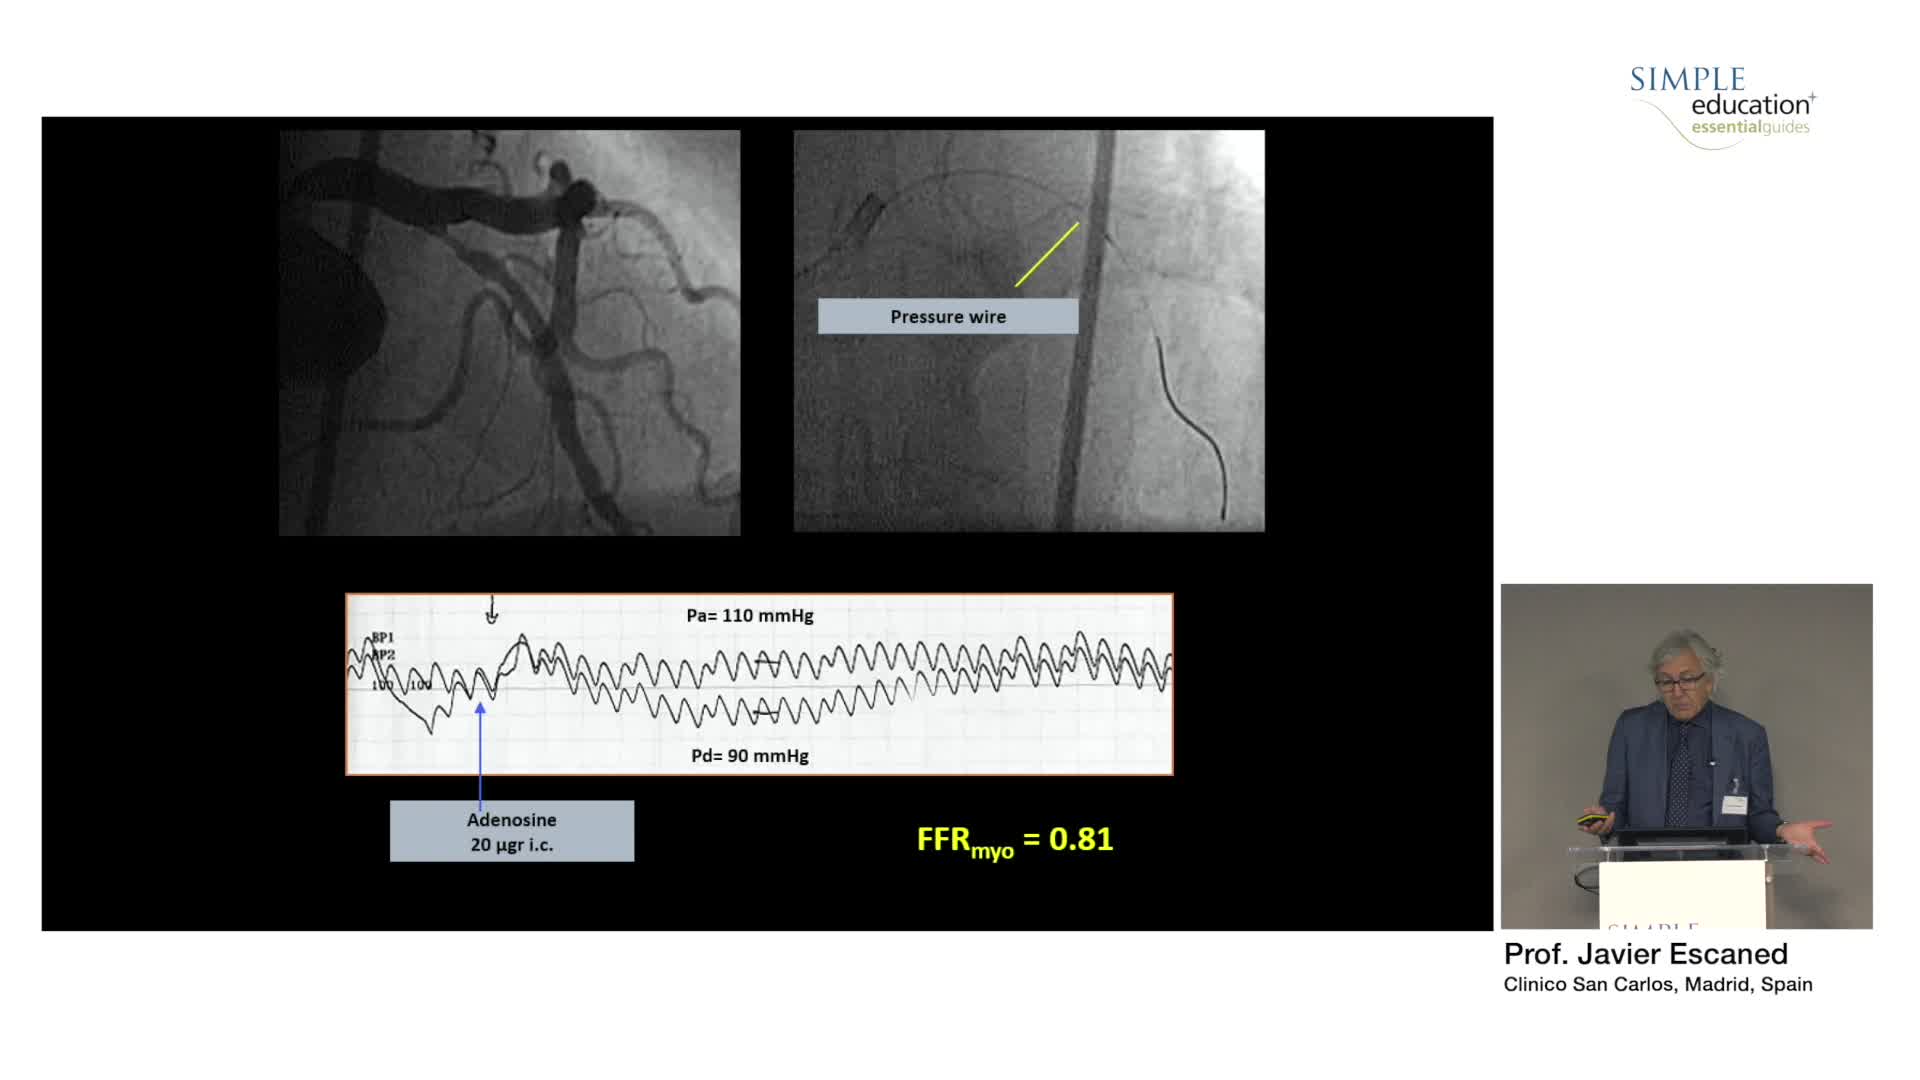

Best practices and personalised medicine in complex PCI - Prof Javier Escaned

Understanding mechanisms of regulation of resting and hyperaemic blood flow, across single and serial stenoses